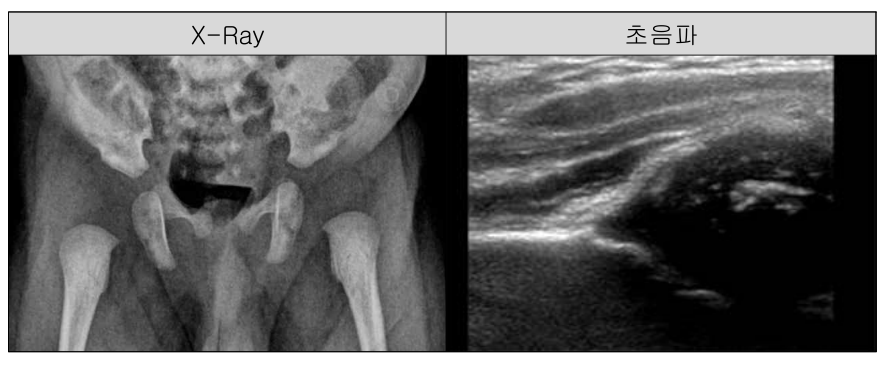

영유아 검진(소아 고관절 이형성증) 초음파 선별 검사용 진단 및 치료 모니터링을 위한 DB 구축

– X-ray사진을 통한 자동 계측 시스템을 통해 위험인자 예측 AI개발 – 초음파를 이용한 Check angle, Alpha angle, Beta angle 측정용 자동 계측 시스템을 통한 DDH 초음파 선별검사용 인공지능 개발

1. 원천데이터